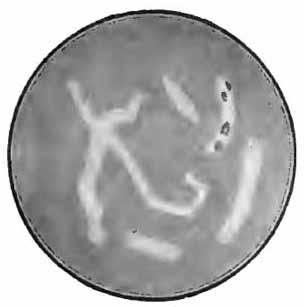

Their recognition depends upon the facts that they are extremely small bacilli; that most of them lie within the pus-cells; that their ends stain more deeply than their centers, sometimes giving the appearance of minute diplococci; and that they are decolorized by Gram's method of staining (Fig. 11).

They are stained blue in Gabbet's method for tubercle bacilli, but are more certainly recognized by Smith's method or by Gram's method, followed by Bismarck brown or fuchsin, as follows:

Bacillus of influenza

FIG. 11.—Bacillus of influenza; cover-glass preparation of sputum from a case of influenza, showing the bacilli in leukocytes; highly magnified (Pfeiffer).